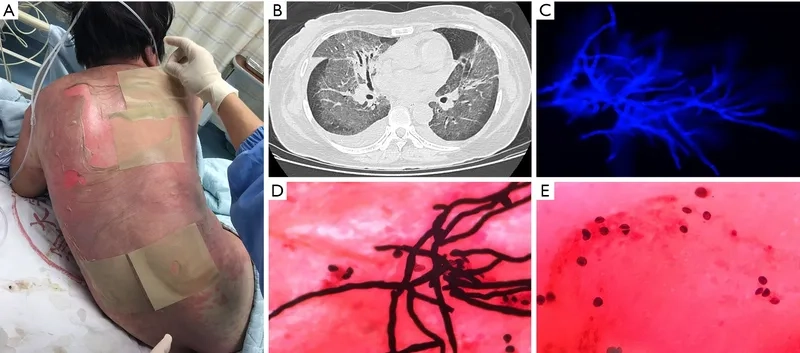

Image of the disease Pneumocystis Pneumonia

A microscopic view of Pneumocystis jirovecii